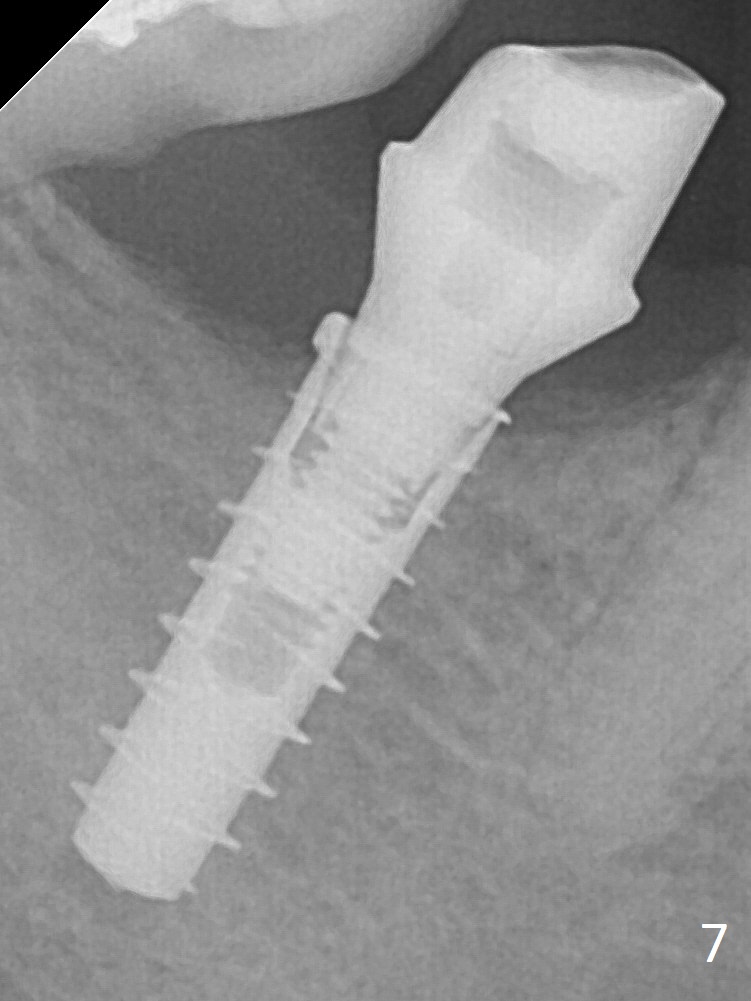

The crown/abutment is loose 2.5 years post cementation due to incomplete abutment seating (Fig.8 < (no clearance between the abutment (A) and the mesial crest (C))). In fact the abutment has been incompletely seated since day one (Fig.5) and remains so 4 months postop (Fig.7). A 6x3 mm healing abutment is placed. When the patient returns, try in the smallest abutment with 2 mm cuff in the Planning Kit and place probably a 4x4(3) mm pair abutment from 5x4(2) mm existing one. Torque and take PA with sensor 1 to confirm seating before impression. Or use 5.5 mm profile drill before reseating the crown/abutment.